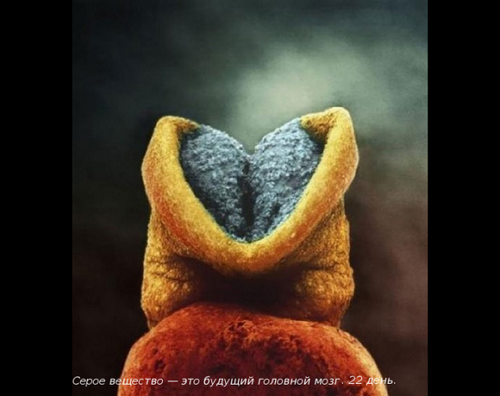

Приблизно в цей же час формується сіра речовина головного мозку.